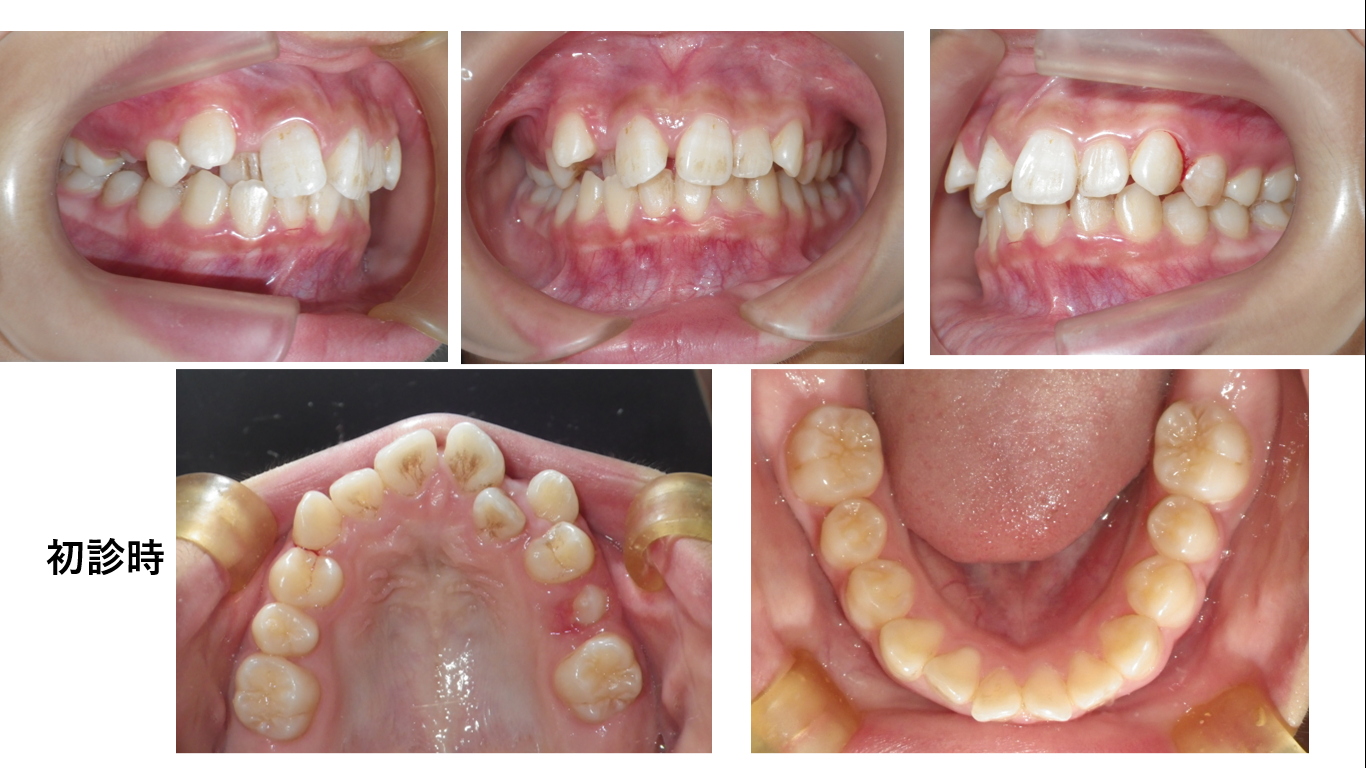

デタラメ矯正(床矯正)の犠牲者が来院

中学3年の女の子が母親と同伴で矯正の相談に当院へ来院しました。母親の説明により、以下の経緯が判りました。小学1年から中学1年まで床矯正した。中1でこれ以上できないからと他院へ紹介された。紹介先の歯科...